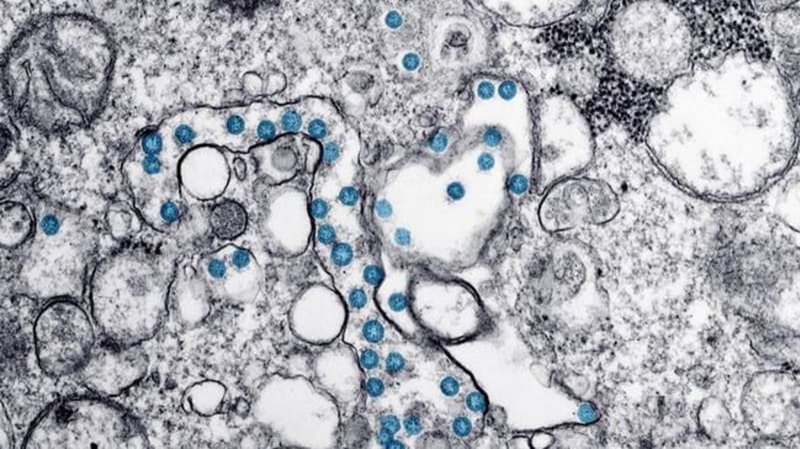

The latest numbers of confirmed and presumptive COVID-19 cases in Canada as of 11:35 a.m. on June 20, 2020:

There are 100,957 confirmed and presumptive cases in Canada.